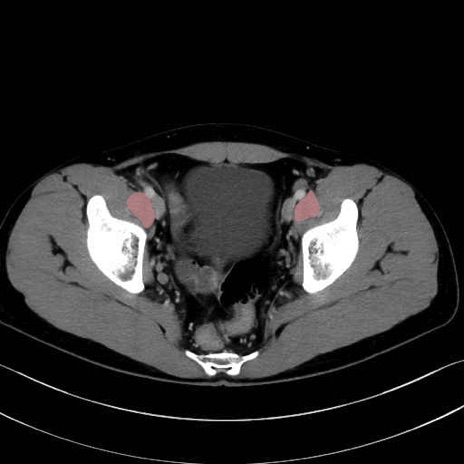

内閉鎖筋 (Obturator internus)